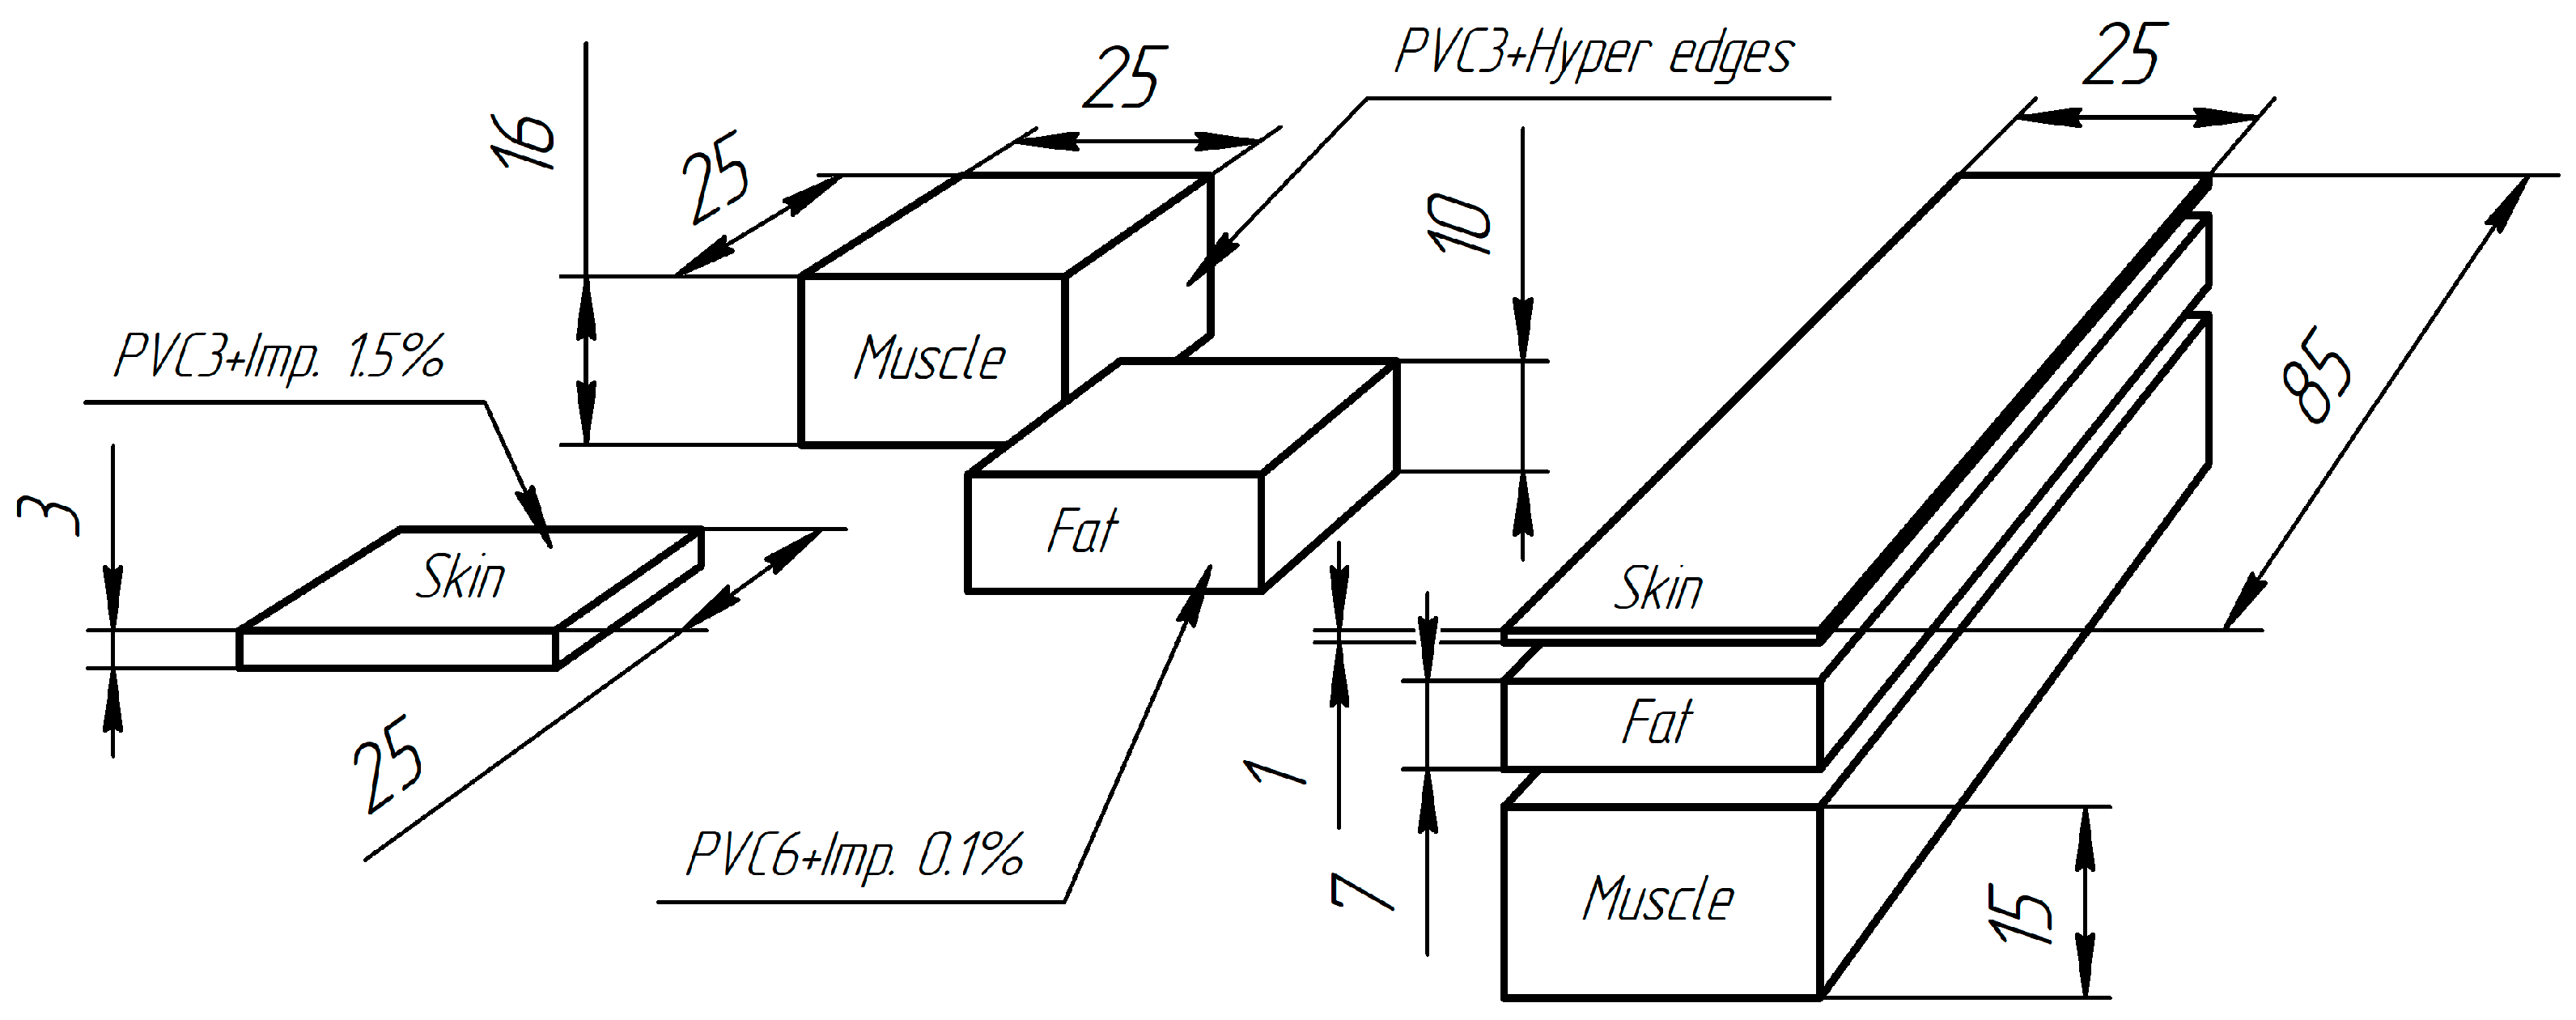

2.4. Soft Tissue Phantom Development

3.2. Verification of the Methodology for Constructing the Soft Tissue Volumetric Models